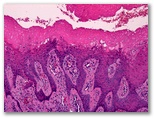

Panadizo herpético ulcerado

Ectima contagioso (Orf)